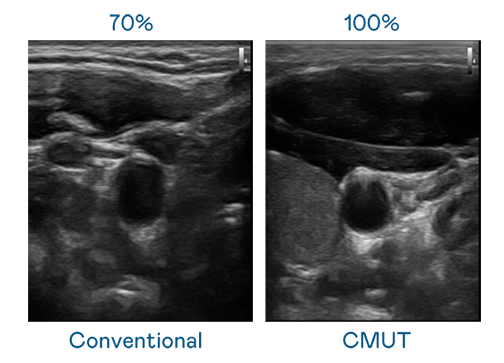

CMUT 技术是一种用电容式微机电元件来产生超音波讯号的技术。与传统 PZT 压电式技术相比,CMUT 频宽增加 30%,更宽频的超音波讯号让影像解析度大幅提升,是实现高影像品质医疗超音波扫描、促进精准医疗发展的关键技术。

大频宽带来超清晰影像

超音波影像的解析度高低,首先取决于探头能发出的讯号频宽。金年会 CMUT 可提供高清晰的超音波讯号,提供高频宽、高灵敏度、影像纹理细节更高的超音波影像,协助医护人员缩短影像判读时间及利用精准的医疗影像进行诊断。